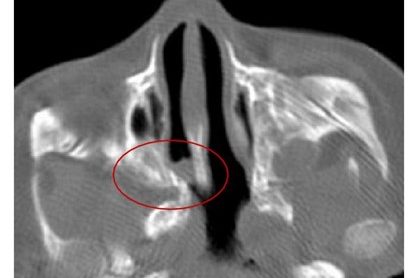

Burun boşluğu ile geniz arasında kalan bölgenin doğuştan tek taraflı veya çift taraflı olarak kapalı kalmasıdır. Normalde doğum sırasında açık olması gereken bu alan, bazen bir zar yapısı şeklinde ince bazen de bir kemik yapı şeklinde sert bir şekilde kapalı kalabilir. Koanal atrezi tek başına olabileceği gibi bazen diğer doğumsal bozukluklarla birlikte de olabilir. Yüz,…